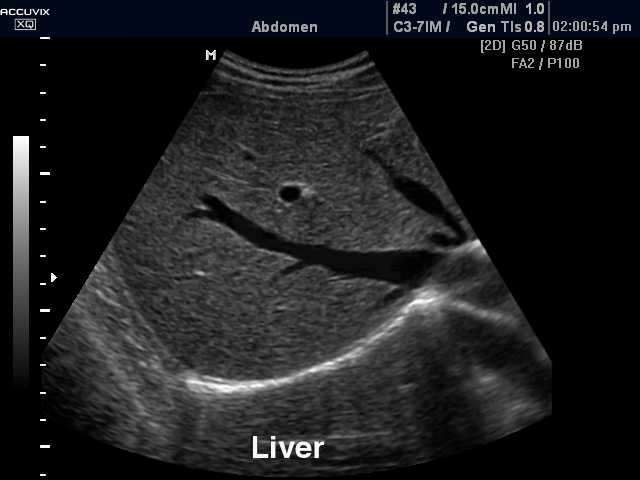

Ultrason

Ultrason ,ses dalgalarından faydalanarak görüntüleme sağlayabilen bir yöntemdir. Ses dalgaları yüksek frekanslı olup insan kulağının işitemeyeceği dalgalardır. Ultrasonun çalışma prensibi, ses dalgalarının farklı doku ve organlardan farklı şekilde yansıması özelliğine dayanır. Tıbbın sadece kadın hastalıkları ve doğum dalında değil hemen hemen b...Devamı İçin Tıklayın

Ultrason, Ultrasonografi, Ultrasound, Ultrason tamiri, 2.el ultrason, USG, Prob tamiri,Ultrason teknik servis